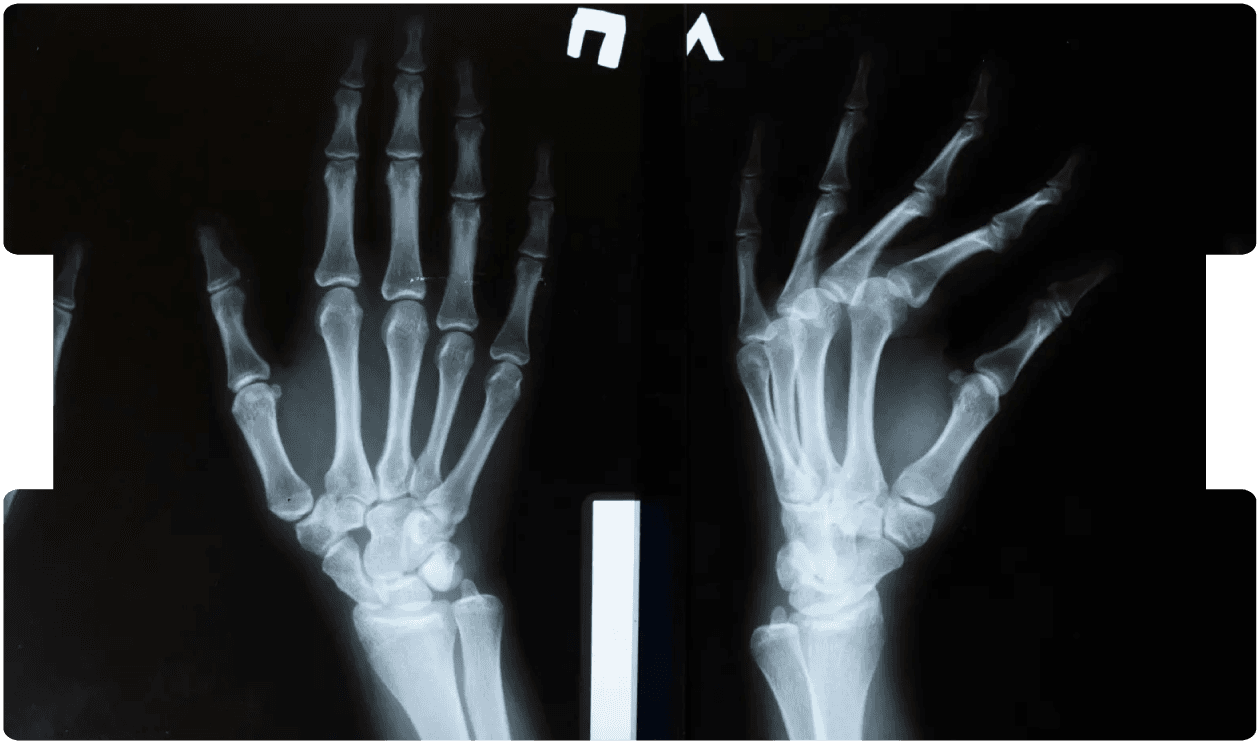

Missed Fractures - A Medico-Legal Experience Over 9 Years

- Missed Fractures

- Scaphoid Fracture

- Fracture Misdiagnosis